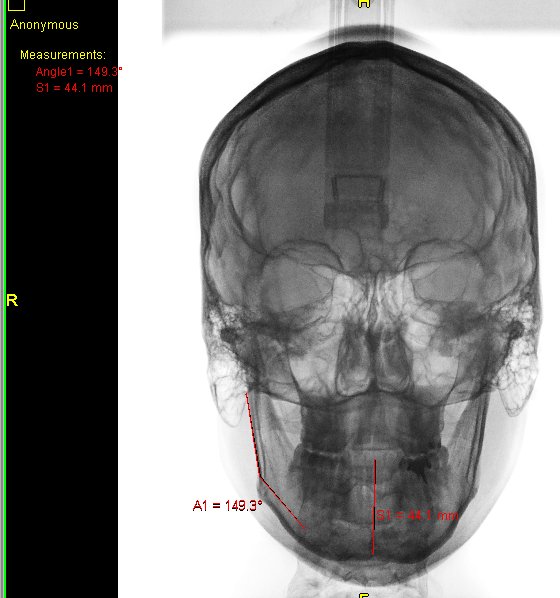

Algunos ejemplos de imágenes digitales

Pulse en las imágenes para ver la ampliación

Se agregó en rojo una medición hecha con la herramienta de medida

14fte 1